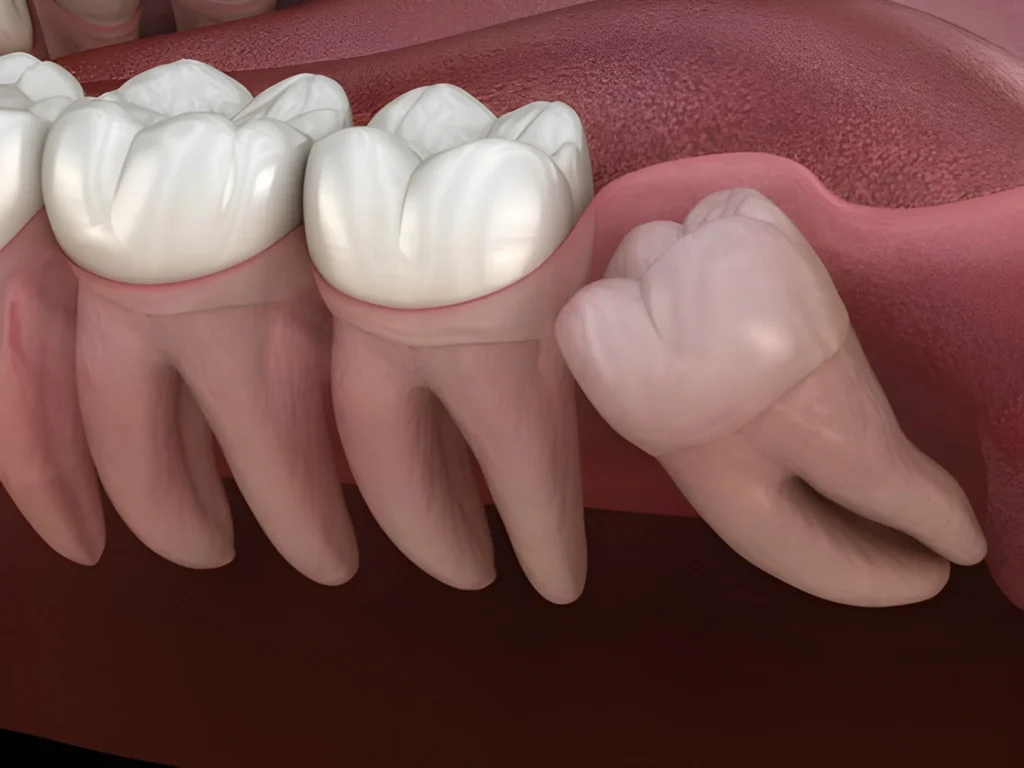

Wisdom Teeth Removal Cost Australia: What You Need to Know

Thinking about getting your wisdom teeth out but not sure what it’ll cost? Most people are in the same boat. Knowing what to expect with pricing helps you plan without any nasty surprises. We’ll walk you through how much it costs to remove wisdom teeth in Australia, why prices differ, and ways to make it […]